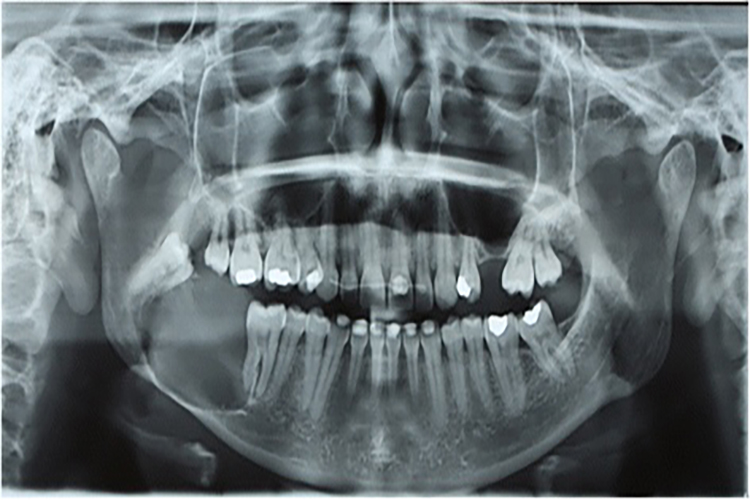

1、成釉细胞瘤:肿瘤生长缓慢,早期呈无痛性、渐进性颌骨膨大,多向侧发展,骨质受压则吸收变薄,压之有乒乓球样感,肿瘤区牙齿可松动、移位或脱落,X线表现为单囊或多囊性破坏,肿瘤区牙根可吸收,可见埋伏牙。常见于30~49岁,平均年龄40岁,男女无明显差异,下颌比上颌多见,下颌磨牙区和下颌升支部为最常见的发病部位。

2、牙源性角化囊性瘤:早期主要沿颌骨前后方向生长,多数患者无明显症状,多在常规Ⅹ线检查时偶然发现,有症状者的早期表现为颌骨膨大。X线表现为单房或多房性透射区,边缘呈扇形切迹。病变多累及下颌磨牙及升支部,常见于10~29岁,男性较女性多见。